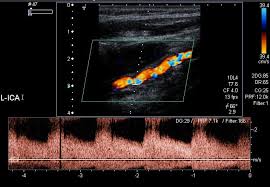

- 젤을 바른 후 초음파 탐촉자를 경동맥 위에 대고 영상 관찰

- 혈류 속도 측정과 플라크 유무 확인

- 플라크 위치와 크기

- 협착률(혈관이 얼마나 좁아졌는지 퍼센트로 표시)

- IMT 수치(혈관 노화 및 동맥경화 지수)

- 혈류 속도 증가 여부